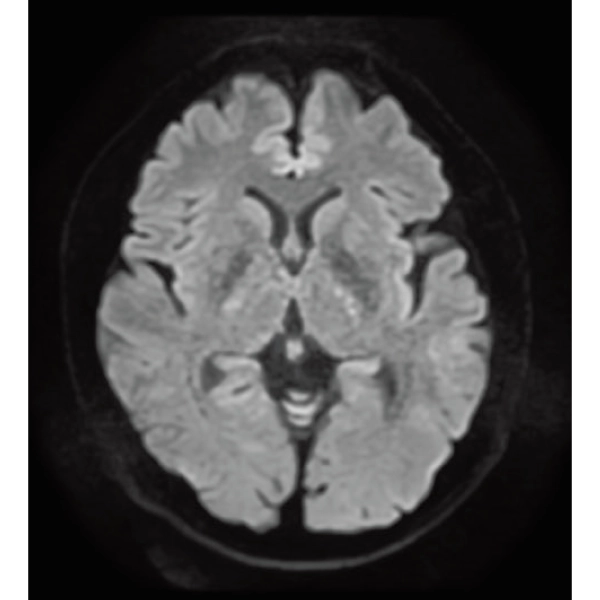

DWI, 0:36